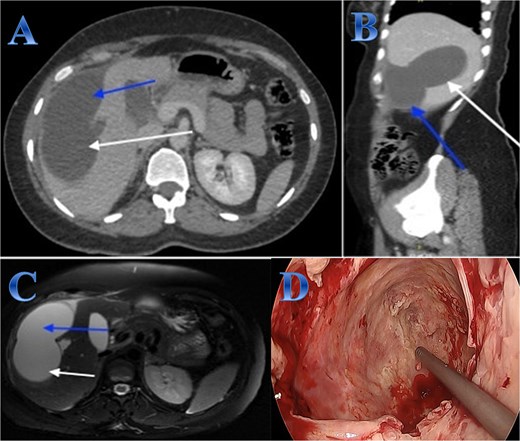

A 54-year-old woman presented with upper abdominal pain with a history of PAIR procedure before 5 years. The abdominal CT scan with contrast highlights left hepatic lobe calcified exophytic CE (Fig. 3).

Case 3. (A) Coronal CT cut of the abdomen at venous phase showing a well-defined cystic lesion (hydatid cyst) seen at the left hepatic lobe, showing calcifications, the lesion seen partially exophytic from the liver and abutting the lesser curvature of the stomach. (B & C) The hydatid cysts that were resected from the liver (C) and from the greater Omentum (B). (D) After resection the liver hydatid cyst was opened to examine the content of the cyst which is showing jelly like structure.

For a left lateral hepatic resection, a subcostal incision allowed exploration of the calcified cystic mass, which affected segments 2 and 3 of the liver and was significantly adhered to the diaphragm and stomach. A left lateral segment (segments 2 and 3) mobilization procedure required dividing the falciform, left triangular, and left coronary ligaments. A harmonic scalpel, in combination with bipolar coagulation, completed the resection of the recurrent hydatid cyst without damaging its internal contents (Fig. 3).